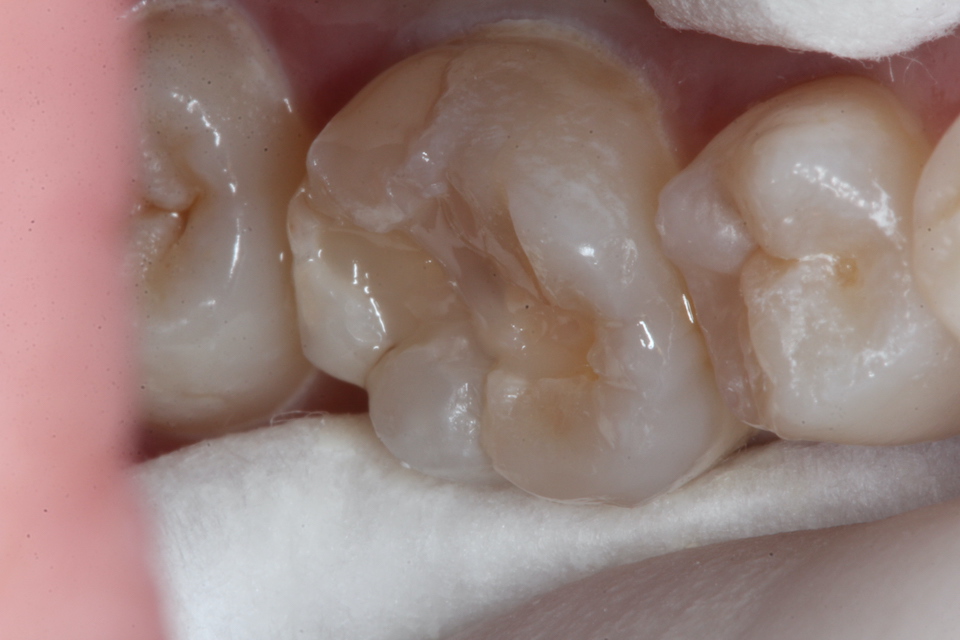

虫歯を除去していく過程

3MIX+α-TCP